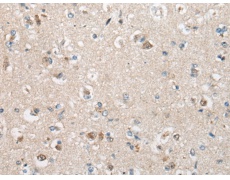

IHC positive control: |

Human brain |